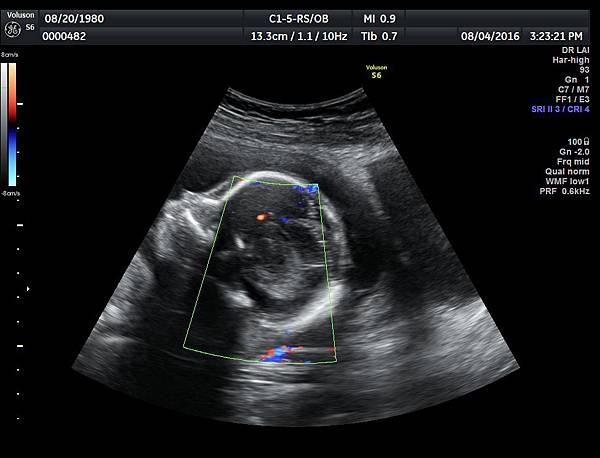

2016年8月4日在執行胎兒高層次超音波檢查時,我發現胎兒腦部的CSP(cavum septum pellucidum)很不清楚(附圖1~4),遇到這種情況,需要仔細評估胎兒腦部的駢胝體,因為CSP的天花板是駢胝體,CSP不明顯時,要合理的懷疑駢胝體沒有發育,或駢胝體下方有長東西(例如lipoma),駢胝體是連接左右大腦的神經纖維所組成。

1. 矢狀切面(sagittal plane):駢胝體呈現類似三明治的中間黑色部分,上面一層薄薄白色的區域是callosum sulcus,打上flow可以看到pericallosum artery在駢胝體上面的周圍,pericallosum artery來源是前腦動脈,參考附圖 6~10,三明治下面白白的部分是和CSP做比較得到的,如果這一層長lipoma(附圖 5),CSP很可能看不到。